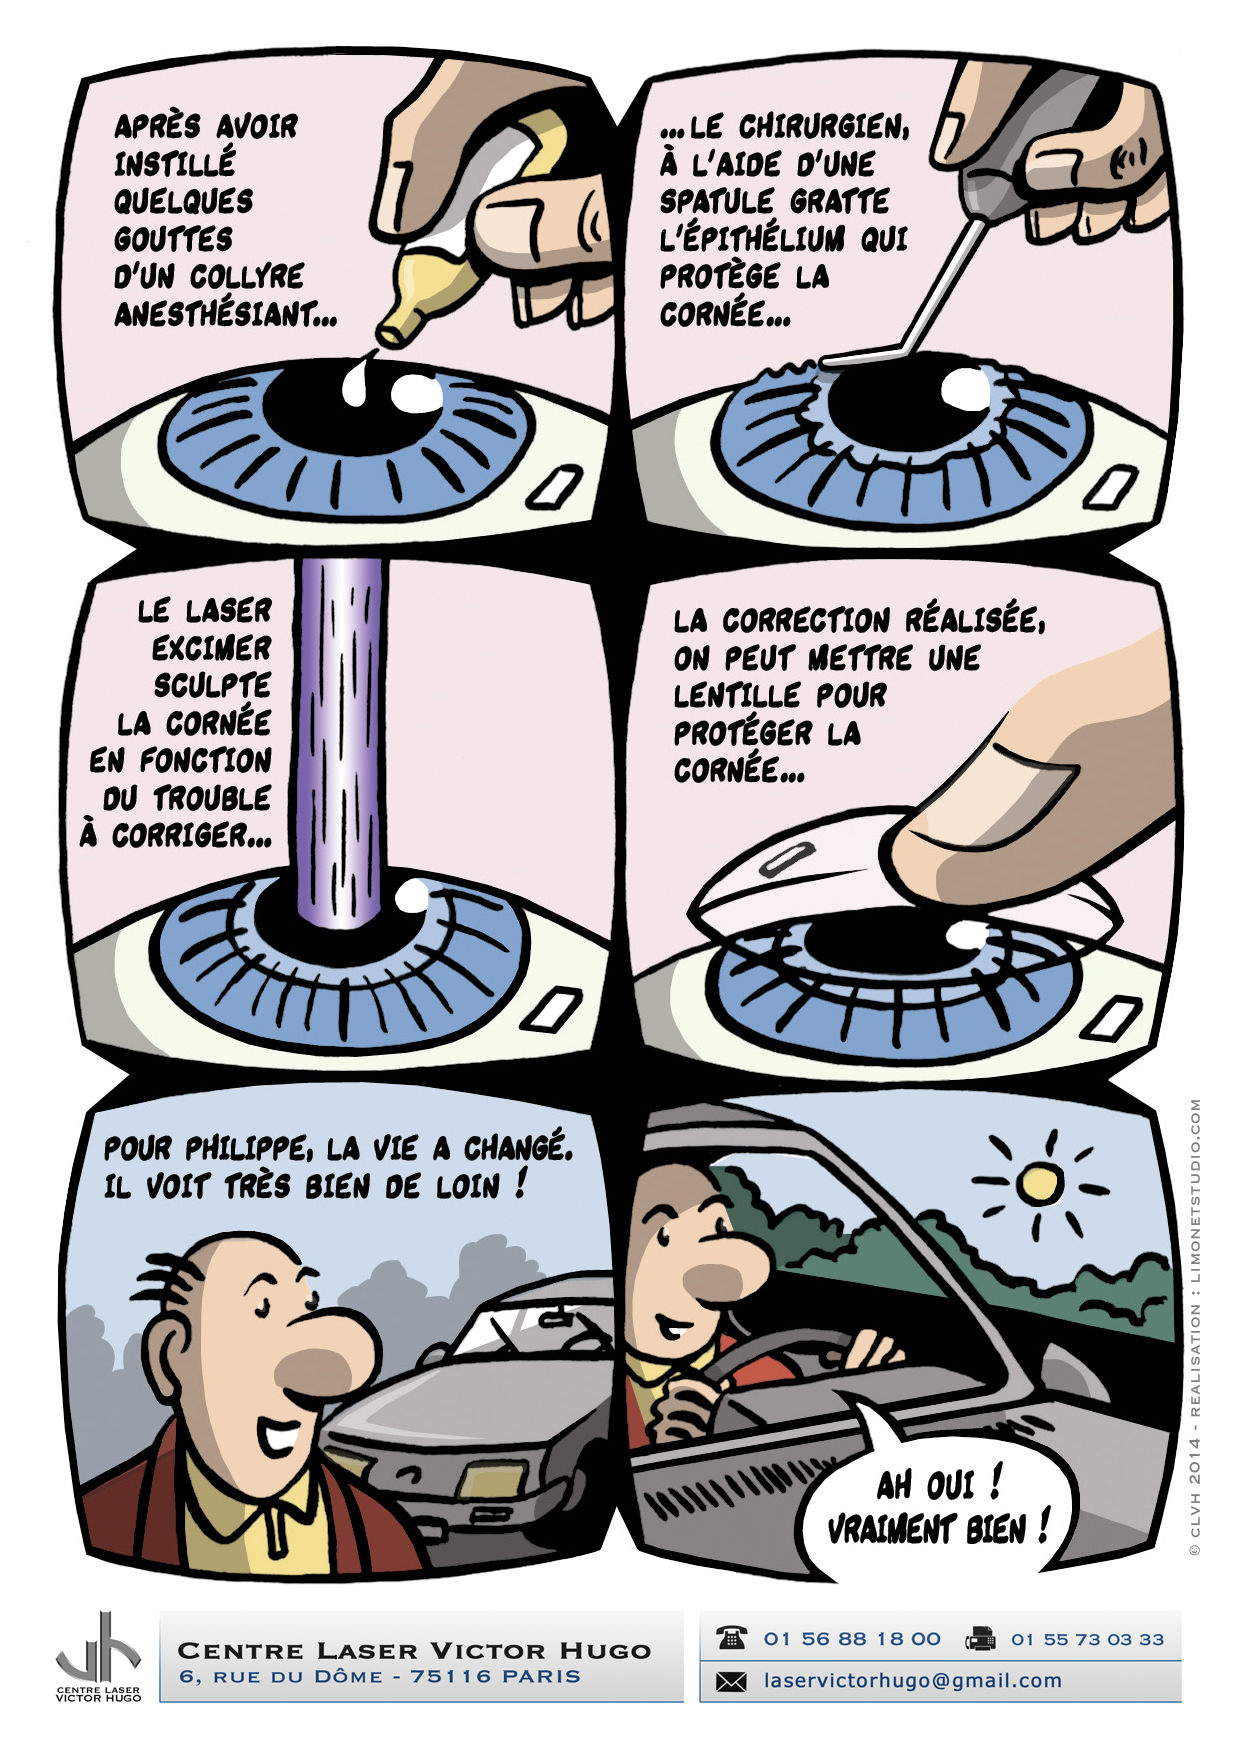

Afin de répondre aux interrogations d'un public de plus en plus intéressé, nous vous proposons cet ouvrage explicatif sous la forme d'une bande dessinée ludique. Cette bédé aborde les troubles de la vision, la chirurgie réfractive (LASIK, PKR et PresbyLASIK), la technique des anneaux et des implants. Cette bébé aborde également l'amblyopie et son traitement orthoptique. Maintenant... à vous de voir !